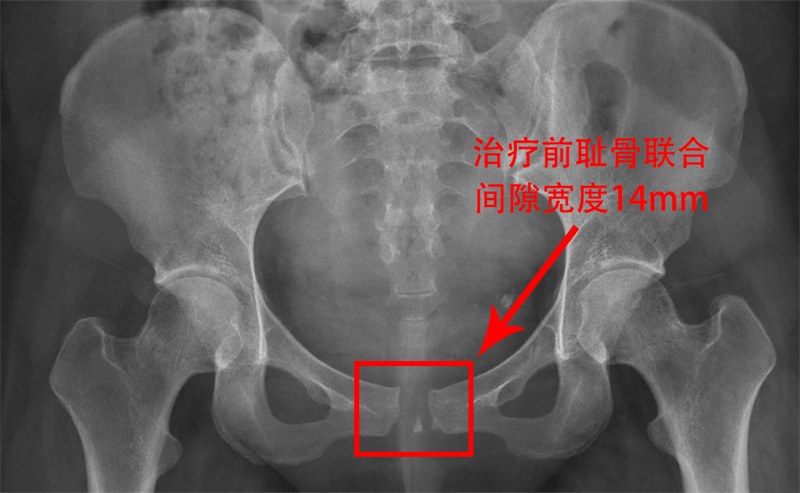

今年年初,剛經(jīng)歷分娩的麥女士在產(chǎn)后7天時(shí),因恥骨區(qū)域劇烈疼痛,連簡(jiǎn)單的翻身、屈腿都變得異常艱難,更不用說正常行走了。在家人的陪同下,她坐著輪椅來到了柳人醫(yī)盆底康復(fù)治療區(qū)就診。經(jīng)過醫(yī)生詳細(xì)詢問病史和查體,結(jié)合骨盆X光檢查結(jié)果,麥女士被明確診斷為恥骨聯(lián)合分離,分離程度達(dá)到了14mm。

恥骨聯(lián)合分離,這個(gè)聽起來有些陌生的名詞,實(shí)際上在孕產(chǎn)婦中并不罕見。正常恥骨聯(lián)合間距為4-5mm,妊娠期婦女生理性增寬3-7mm,而當(dāng)分離程度>10mm時(shí),即可診斷為恥骨聯(lián)合分離。患者往往會(huì)出現(xiàn)恥骨聯(lián)合、腹股溝區(qū)疼痛,活動(dòng)受限,甚至出現(xiàn)搖擺步態(tài)。雖然其發(fā)生率僅為1/300-1/30000,但一旦發(fā)生,卻會(huì)給寶媽們帶來極大的痛苦和不便。

令人欣喜的是,經(jīng)過5次治療,麥女士的疼痛基本消失,行走自如,無搖擺步態(tài)。治療后4月余復(fù)查骨盆X光顯示,恥骨聯(lián)合已經(jīng)無分離,且沒有出現(xiàn)反彈的情況。麥女士終于恢復(fù)了往日的活力,重新?lián)肀Я私】档纳睢?/p>